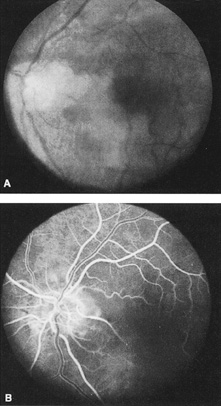

Ophthalmic artery obstruction is characterized by an initial opacification of the entire retina in a manner similar to that of central retinal artery obstruction (Fig. 4A). The cherry-red spot may or may not be present, however.119 The difference between an ophthalmic artery obstruction and central retinal artery obstruction is that in an ophthalmic artery obstruction, with time, optic atrophy develops, as does varying amounts of pigmentation due to the lack of perfusion of the retinal pigment epithelium (see Fig. 4D). This pigment is generally diffusely scattered throughout the posterior pole but it may also be seen in greater amounts in the periphery.

Fig. 4. A: Ophthalmic artery obstruction showing a cherry-red spot: the visual acuity was no light perception. B: At 26.2 seconds, the retinal vessels are filled, but no dye is seen in the choroidal circulation. C: By 37.7 seconds, the choroidal circulation is more visible, and a doughnut-shaped area of hypofluorescence is noted. D: Six months after the initial photographs, optic atrophy is present, as is atrophy of the retinal vessels. Diffuse pigment disturbance is evident.

Intravenous fluorescein angiography generally shows moderate to marked abnormalities in the filling of the choroid, in addition to a delay in filling or even nonfilling of retinal vessels (see Fig. 4B and 4C). Staining of the retinal pigment epithelium can also be seen; this staining either can occur locally in the macular area or it can be diffuse.119 The electroretinogram shows abnormalities of both a- and b-waves, reflecting ischemia to both the inner and outer retina. Almost all reported patients have had an initial visual acuity of no light perception; virtually no patients can be expected to have a final visual acuity better than that.119 An acuity of no light perception is a clue to the presence of an ophthalmic artery obstruction. Because relatively few patients with central retinal artery obstruction have an initial visual acuity of no light perception, no light perception usually suggests the likelihood of some obstruction of the choroidal circulation.14

We have seen several patients with anterior ischemic optic neuropathy with suspected temporal arteritis where the Westergren sedimentation rate and C-reactive protein were normal and the intravenous fluorescein angiogram helped confirm the diagnosis (Fig. 5).